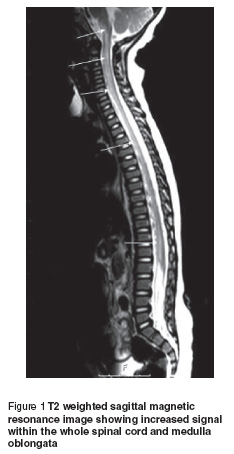

In order to rule out spinal cord pathology, craniospinal magnetic resonance imaging (MRI) was obtained immediately. On T2 weighted images, a diffuse, symmetrical increased signal within the whole spinal cord was observed. Lesions showed no contrast enhancement (Figure 1). Contrast-enhanced MRI angiography demonstrated normal vascular structures. No other abnormality was detected. Cranial MRI revealed no abnormality.